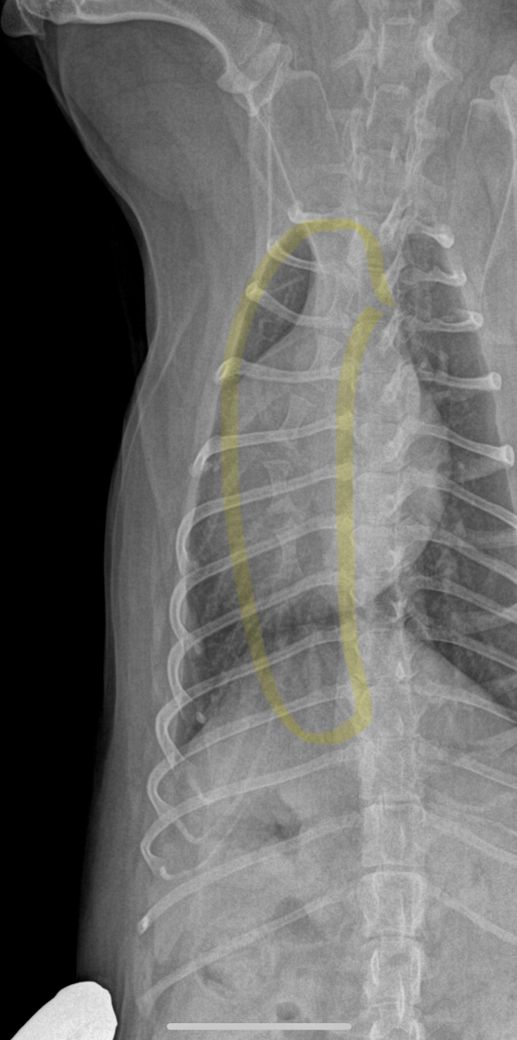

엑스레이는 흉골이 휜거같아 이상해서 세번정도 찍었다고 하네요. 사진 보면 노란색 표시 흉골이 휘어있고 심장도 쏠려있습니다…잘못찍었다고 흉골이 휘고 심장도 쏠릴 수 있나요?!?

첫번째 사진이 1년전 다른병원에서 찍은 엑스레이고 2,3번째가 이번에 찍은 흉골 휜 엑스레이입니다.. 3,4번째 흉골 휜 엑스레이 같은 사진인데 휜 흉골부분 노란색으로 표시해뒀습니다. R, L사진 둘 다 다른방향에서 찍은거같은데, 둘 다 휘어있습니다. 폐쪽의 문제일수도 있을까요? 기침이나 식욕감퇴 등의 다른 증상은 없고 변 상태도 좋습니다.